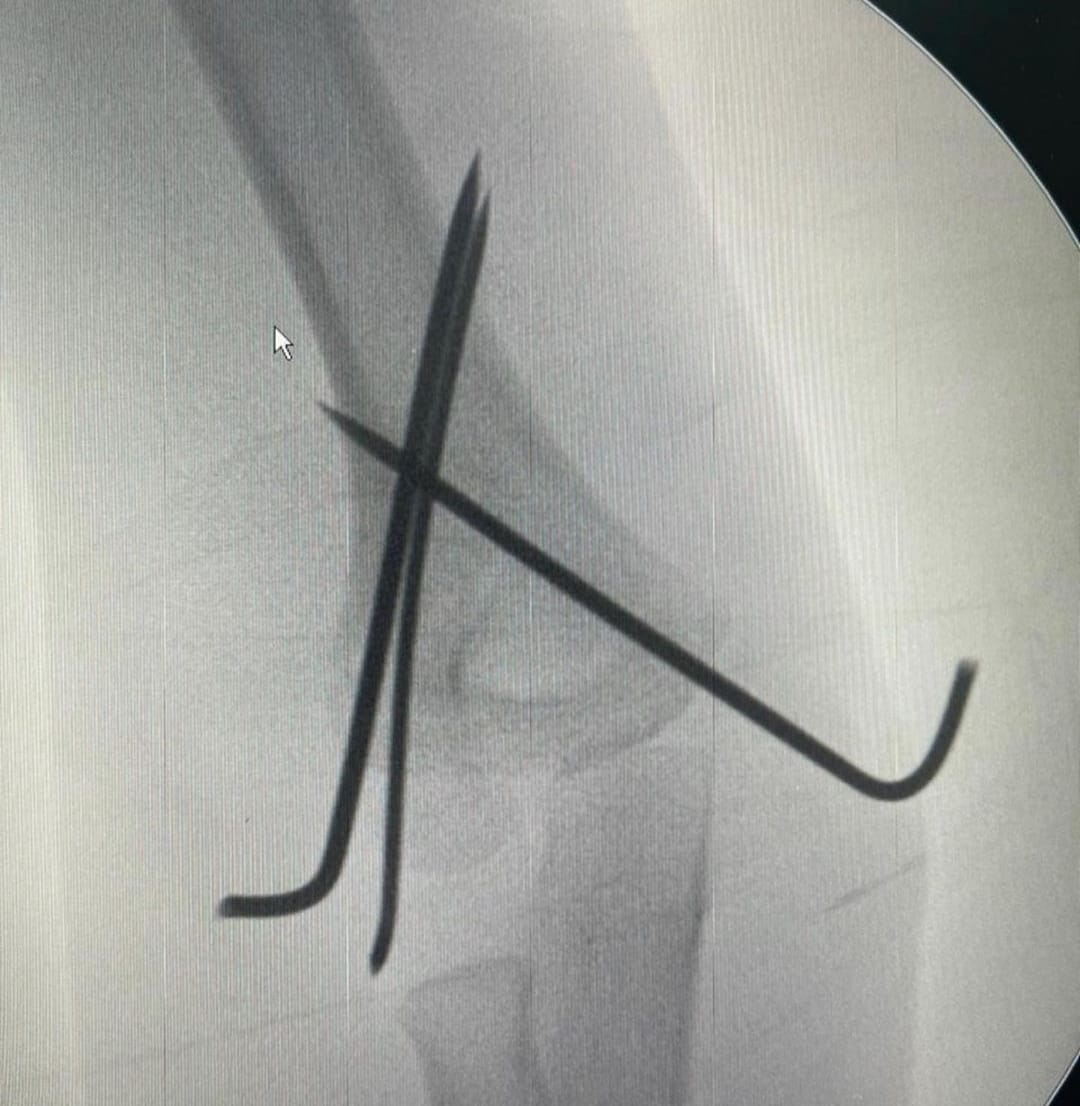

- Minimally invasive techniques

- External fixation